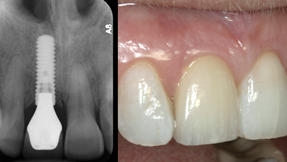

Dental Implants The ideal tooth replacement

Whether teeth are lost to an accident, disease or have been missing since birth, dental implants are the next best thing to natural teeth. A dental implant is placed in the jaw to replace the missing tooth root. Implants look and feel like your natural teeth, and can help prevent bone loss and protect adjacent teeth.

Anterior Implants (Front Teeth) using the SMILE™ Technique

For anterior (front) teeth, Dr. Henshaw follows the protocol of the SMILE™ Technique developed by Dr. Dennis Shanelec. He has been personally trained in this technique by Dr. Dennis Shanelec at the MTI, Microsurgical Training Institute. SMILE Technique Implants are a state-of-the-art method for esthetic tooth replacement. The SMILE Technique employs minimally invasive extraction, immediate implant placement, and a temporary crown to preserve your natural smile. The temporary crown emerges from the gum exactly like a natural tooth. This supports the gum to maintain tissue height and shape for ideal esthetics. Patients are never without a tooth and can avoid multiple surgeries with removable temporary teeth.